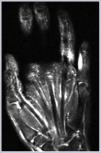

En cuanto a su diagnóstico, la principal herramienta para establecerlo es la exploración física, mediante la positividad de 2 signos clínicos18. En el primero, denominado «signo de la oración», el paciente es incapaz de oponer por completo las superficies palmares de los dedos, al no lograr la extensión completa de las articulaciones metacarpofalángicas e interfalángicas proximales con las manos en posición de rezo (fig. 1), mientras que en el segundo, denominado «signo de la mesa», existe una incapacidad para apoyar la mano totalmente plana sobre la superficie de una mesa (fig. 2)19. Ambos signos constituyen buenas pruebas clínicas para el cribado; sin embargo, el empleo del goniómetro para la medición de la restricción articular sigue siendo el «gold standard» en la exploración. Con el fin de valorar y seguir la progresión de la rigidez que presenta una mano con LMA, se ha descrito un sistema de clasificación que la divide en 4 estadios (tabla 1)20.